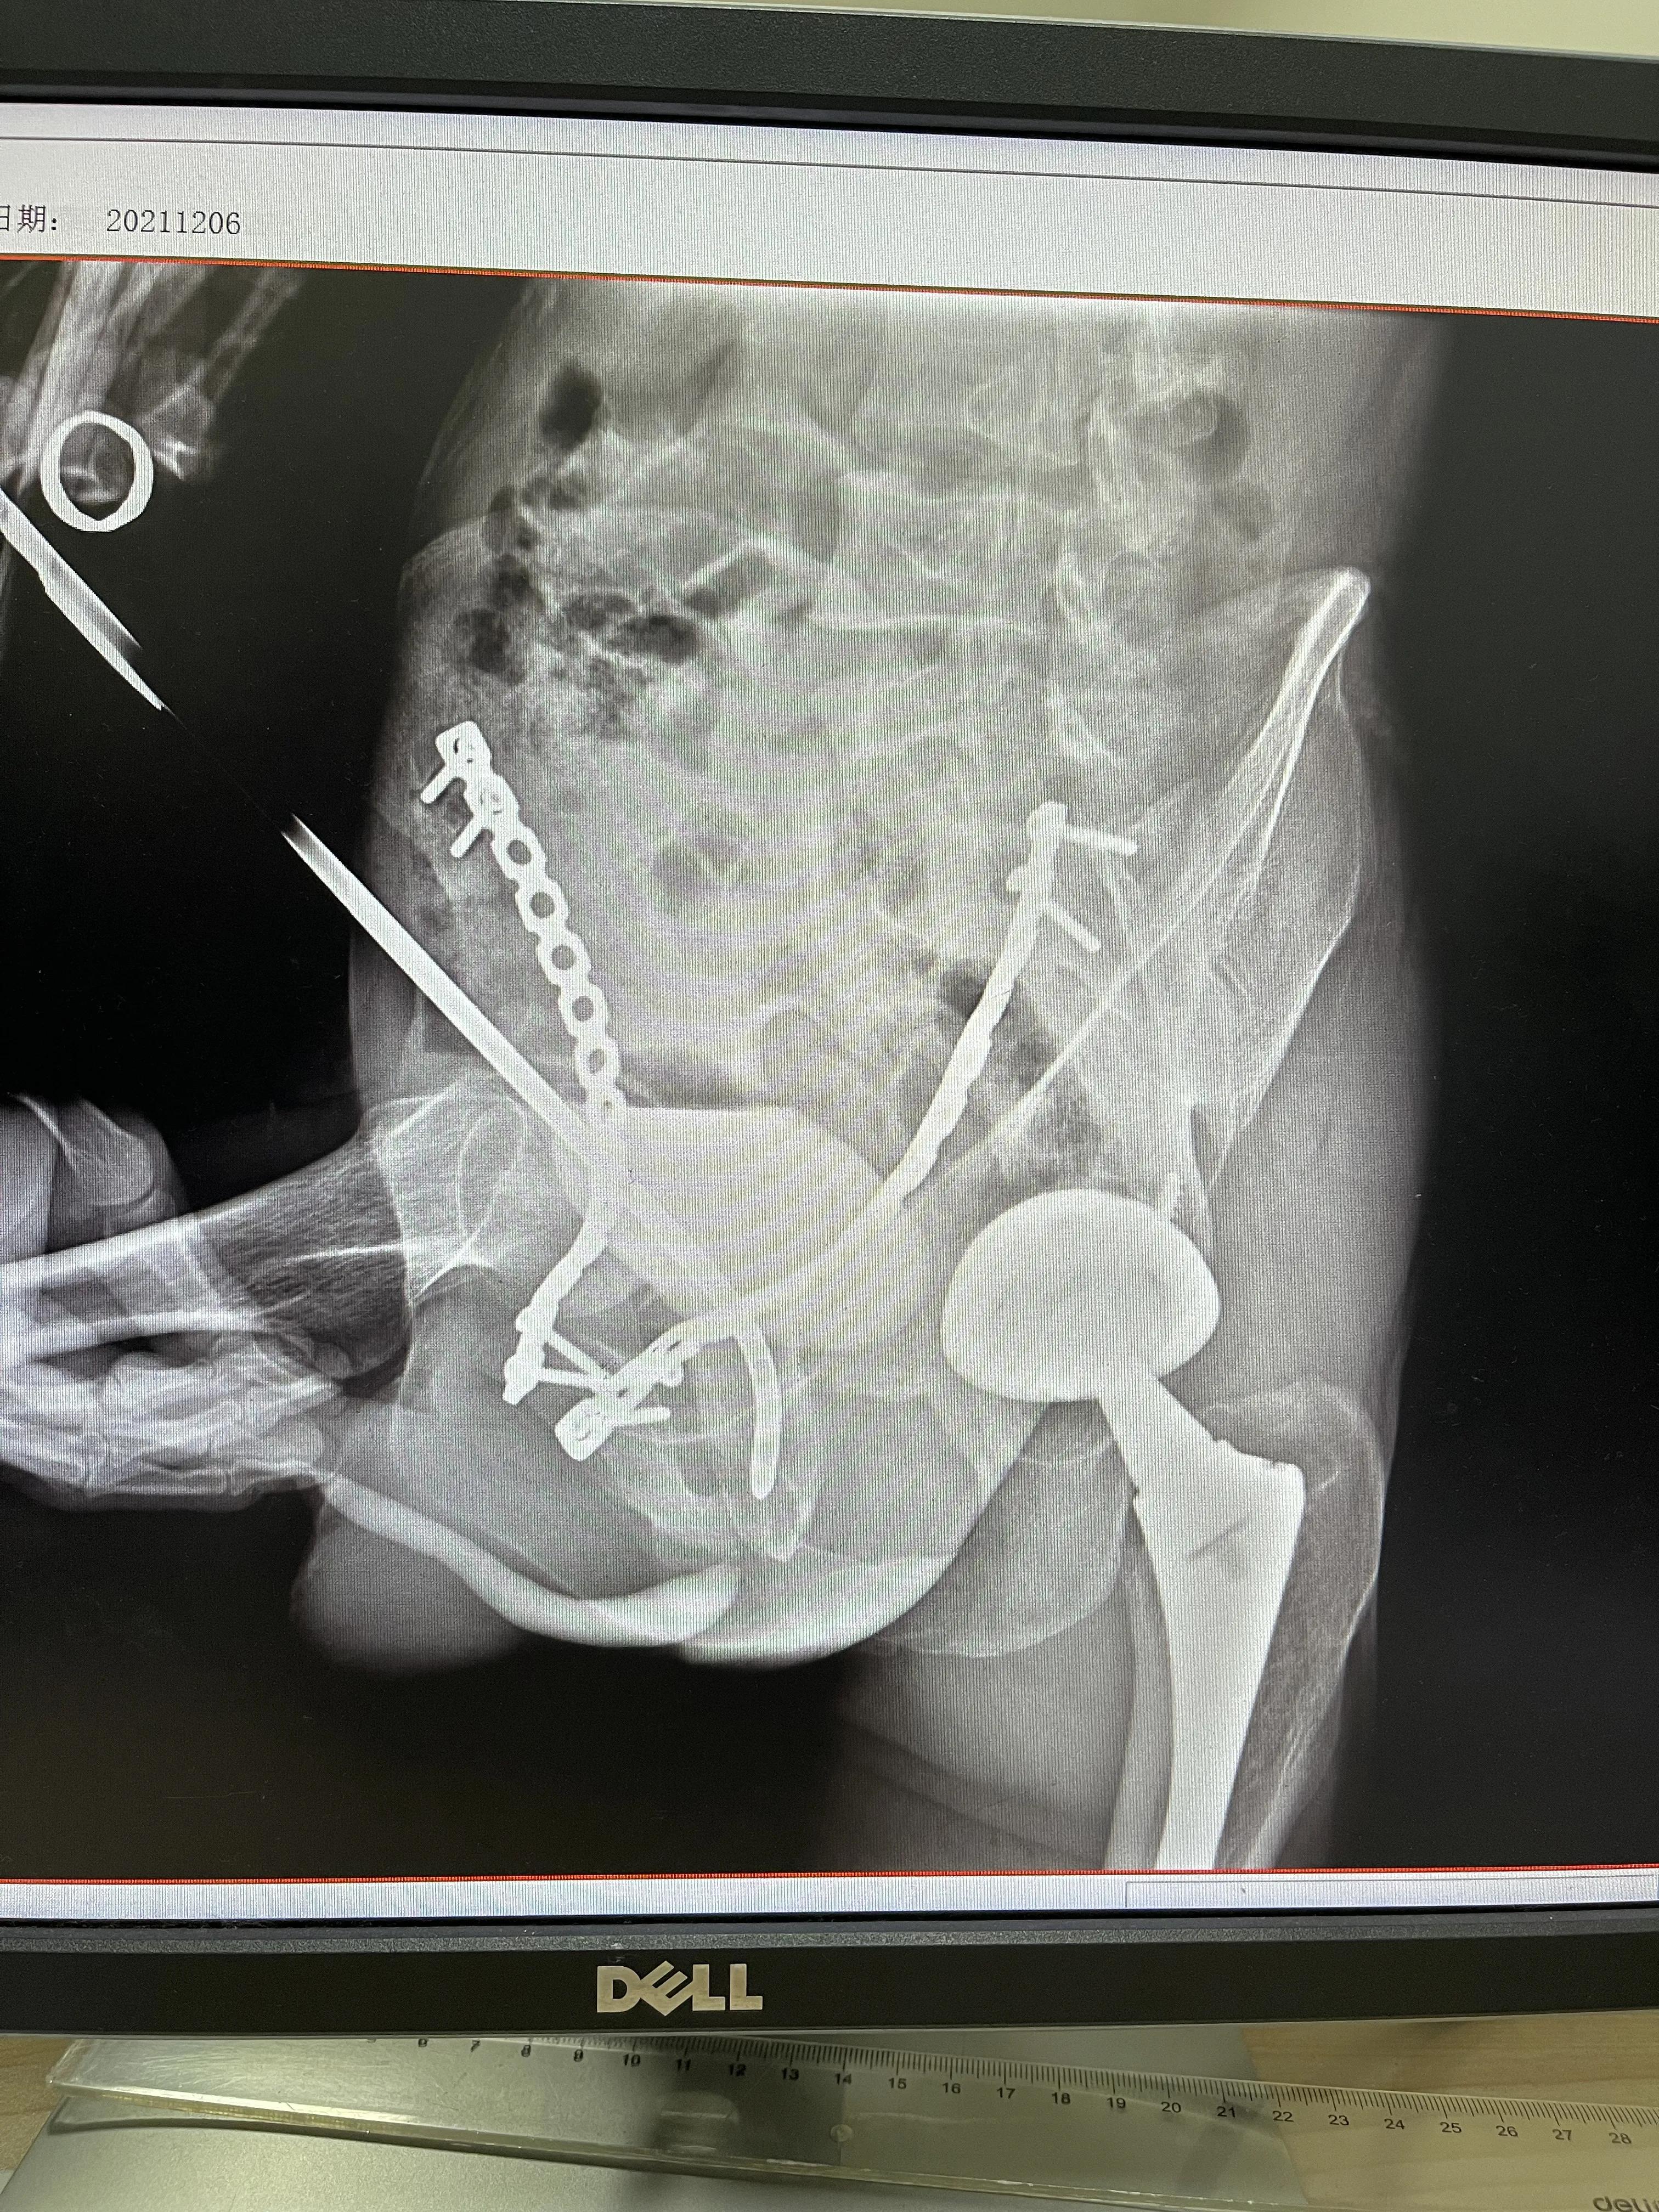

2021年12月,患者慕名前来我的工作室诊治,经过“膀胱尿道会师造影”,发现膜部尿道闭锁2厘米(图一)。如果采用开放性手术“尿道疤痕切除端端吻合术”,手术难度极大,顶级专家都要做3个小时左右,甚至5~6个小时。复发率很高,达到10~50%。因为有会阴部大切口(甚至有下腹部长切口),还可能发生大出血(出血量几百毫升甚至上千毫升)、切口感染、尿道会阴瘘、损伤直肠导致“尿道直肠瘘”,1/3患者损伤膜部尿道两侧的勃起神经和动脉导致“阳痿”等严重并发症。

阿先生的手术仅仅用时65分钟,出血量20毫升,留置F22导尿管2个月(图二)。拔管后排尿通畅,平均尿流率12毫升/秒(图三,达到正常小伙子水平),无尿*禁失**,未发生阳痿。扩张尿道4次,F24尿道探子顺利无阻力通过。康复治疗一周后,目前患者已经治愈。

图一 术前膀胱尿道会师造影:膜部尿道闭锁

图二 术比,膜部尿道通畅